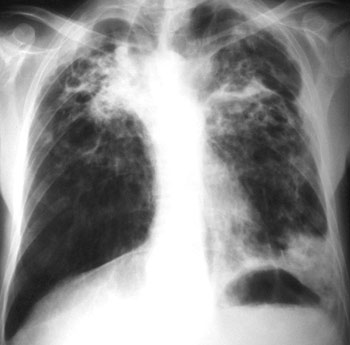

La tuberculosis, antiguamente denominada tisis, es una enfermedad bacteriana que afecta a los pulmones. Recibe este nombre debido a la formación de "tubérculos", es decir, orificos en la cavidad pulmonar.